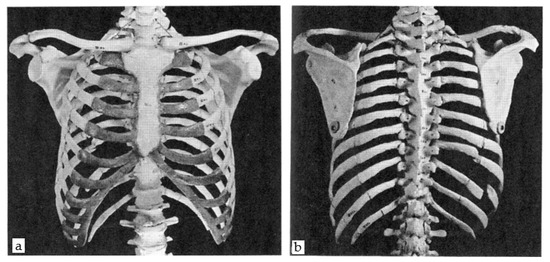

2.1.1. The Thorax

2.1.2. The Shoulder Girdle

2.2.1. Generic Model–Ribs Model

2.2.2. Generic Model–Sternum Model

2.2.3. Generic Model–Clavicle Model

2.2.4. Generic Model–Scapula Mode

3.1. 3D Modelling of Thorax without Any Scoliosis-Related Deformity